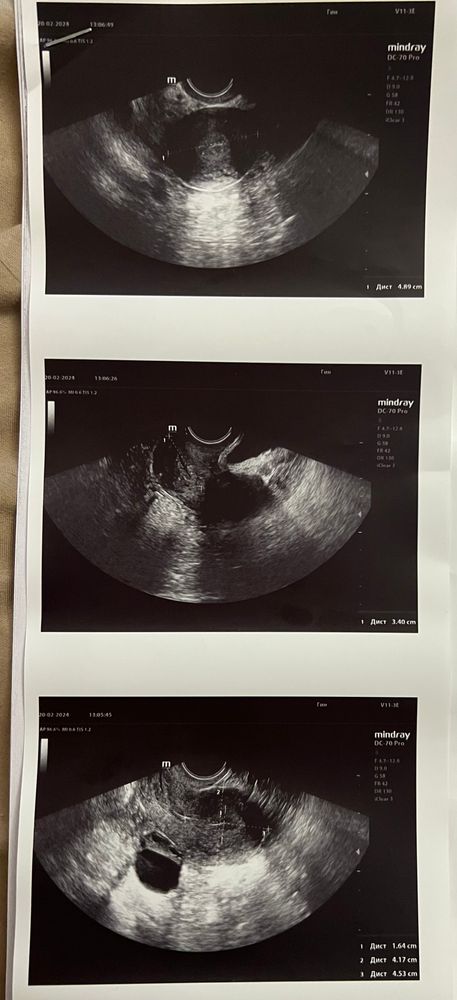

Всем привет! Девочки, помогите разобраться что означает заключение и фото , пожалуйста

гинеколог сказала овуляция была примерно 4 дня назад тк фолликул лопнувший. Свободная жидкость есть, мало.

меня смущает отсутствие ЖТ, и размеры фолликулярной кисты 3 см

Главатских Катерина, так вот она сказала что вероятно была 4 дня назад, поняла она это исходя из свободной жидкости и крови около фолликула, говорит фолликул перерос и вероятно лопнул. Я вот хотела узнать кто что по снимкам узи может сказать

Так ведь на снимке узи видно что фолликул лопнул, гинеколог сказала около него есть немного крови и есть свободная жидкость . Вот я не понимаю как это все